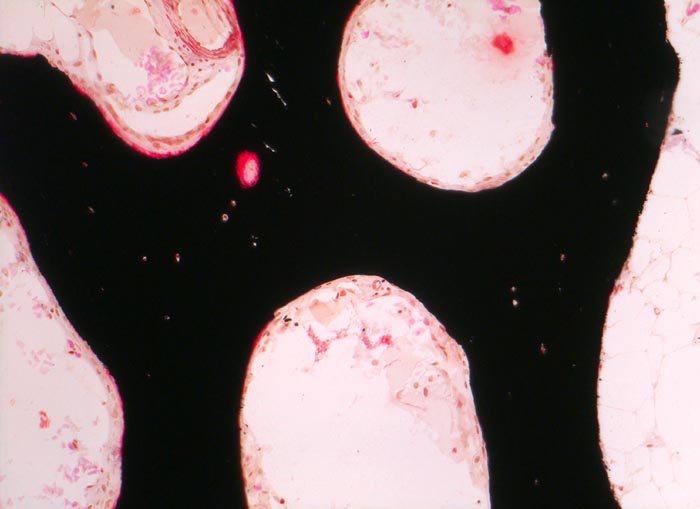

Bei Vitamin D Mangel ist das Gesamtvolumen sowie die Menge des Osteoids auf der Oberfläche der Spongiosabälkchen vermehrt (Volumen- bzw. Oberflächenosteoidose). Wechselt das Angebot an Vitamin D, kann unmineralisiertes Osteoid auch von mineralisierter Matrix eingeschlossen werden (= begrabenes Osteoid ( 3517)). Verbreiterte Osteoidsäume können neben der Osteomalazie (bzw. der Rachitis im Kindesalter) auch bei Hyperparathyreoidismus, bei einer fibrösen Dysplasie oder bei schnell wachsenden knochenbildenden Tumoren beobachtet werden. Insbesondere bei metabolischer Ursache sind die histologischen Veränderungen häufig kombiniert mit Veränderungen einer Fibroosteoklasie, bei der es zu oft tunnelierenden osteoklastären Resorptionen des Knochens und konsekutiver Auffüllung mit einem gut vaskularisierten bindegewebigen Stroma kommt. Die radiologisch nachweisbaren Looser-Umbauzonen (benannt nach dem Schweizer Chirurgen E. Looser) entsprechen Arealen unvollständig durchgebauter Fissuren/Frakturen mit nicht mineralisiertem Faserknochen. Durch eine Tetrazyklinmarkierung in zeitlich definiertem Abstand vor einer Knochenbiopsie kann die Mineralisationsdynamik abgeschätzt werden, da Tetrazykline bei der Mineralisation in den Knochen miteingebaut werden und im Fluoreszenzmikroskop identifiziert werden können.